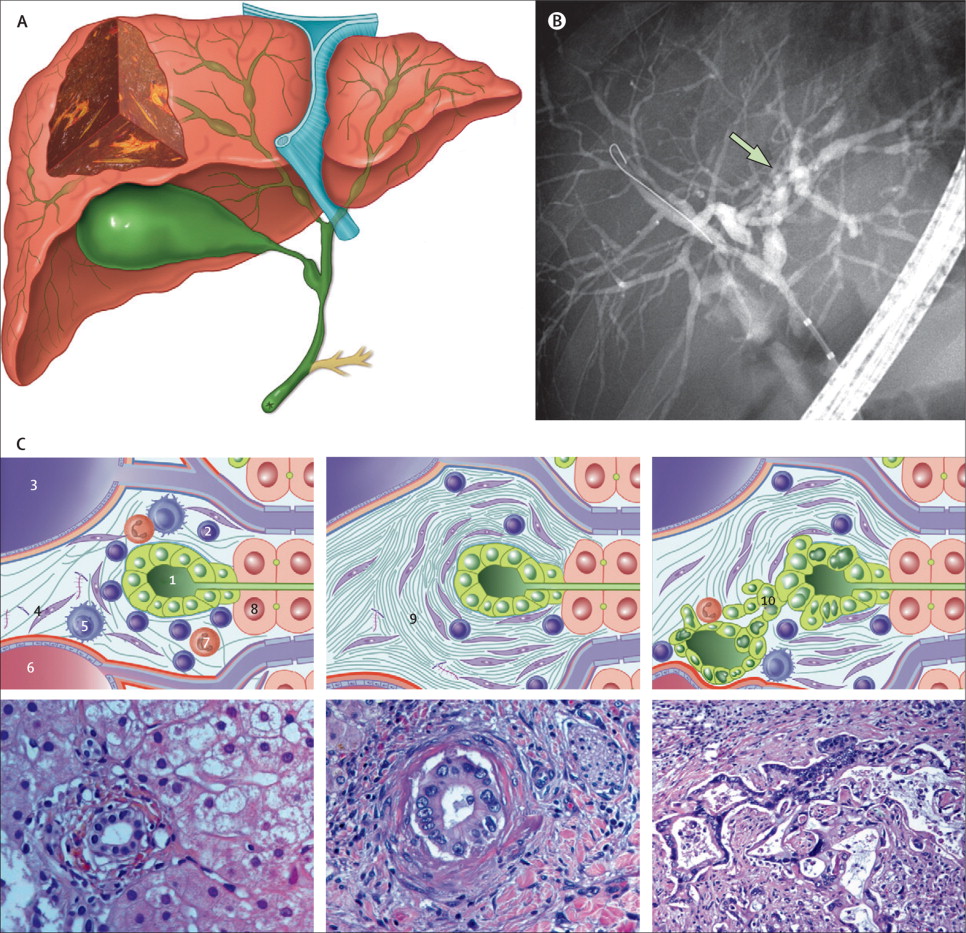

Фотографии и изображения, связанные с симптомами первичного склерозирующего холангита